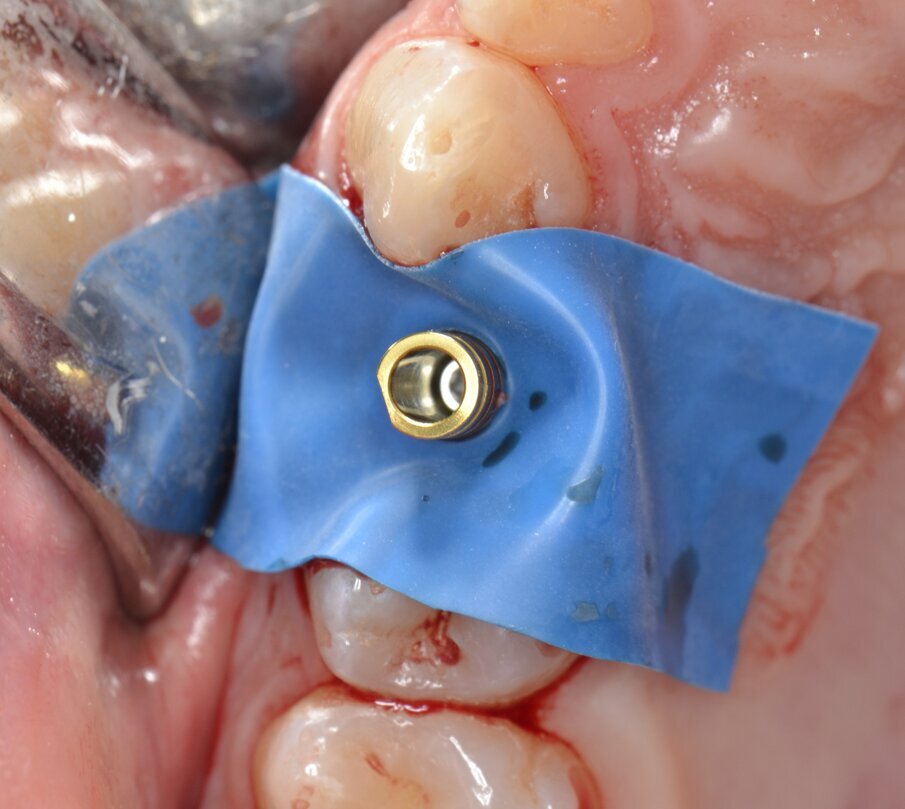

Viene inserito un impianto di tipo “bone level” da 3,5 x 15 mm: il raggiungimento di un torque di inserimento implantare (IT) superiore a 55 N.cm pone l’indicazione ad una procedura di provvisorizzazione immediata, motivo per cui un temporary abutment con una connessione protesica di tipo “platform switching” viene avvitato all’impianto con un torque di 35 N.cm (Figg. 10, 11). Per contrastare l’inevitabile contrazione dell’alveolo postestrattivo, il gap peri-implantare viene innestato con un biomateriale di origine eterologa (Figg. 12, 13). L’innesto viene eseguito con un leggero overbuilding in senso verticale allo scopo di sostenere il margine gengivale (Fig. 14).

Dopo aver protetto il sito chirurgico mediante un frammento di diga sterile (Fig. 15) una corona provvisoria in resina viene adeguatamente ribasata sul temporary abutment avvitato all’impianto, avendo cura di evitare qualsiasi tipo di contatto sia in occlusione centrica che durante i movimenti di lateralità e protrusione (Figg. 16, 17). Prima di dimettere il paziente con la corona provvisoria in situ, viene eseguito un esame radiografico endorale di controllo: trattandosi di un impianto “bone level” è consigliabile inserirne la piattaforma implantare circa 0,5 - 1 mm apicalmente alla cresta ossea marginale (Fig. 18).

Fig. 15 - Protezione del sito chirurgico mediante un frammento di diga sterile prima di effettuare la ribasatura della corona provvisoria.